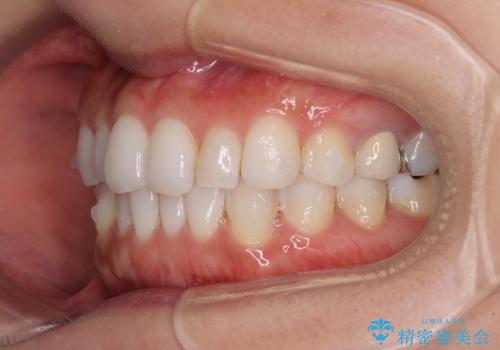

軽度の叢生をインビザライン・ライトで解消

- 前歯が気になるとのことで来院された患者様です。

歯列不正は軽微であったため、インビザライン・ライトにより、費用を抑えて矯正治療を行うこととしました。

短期間で気になる前歯の歯列を改善することができました。